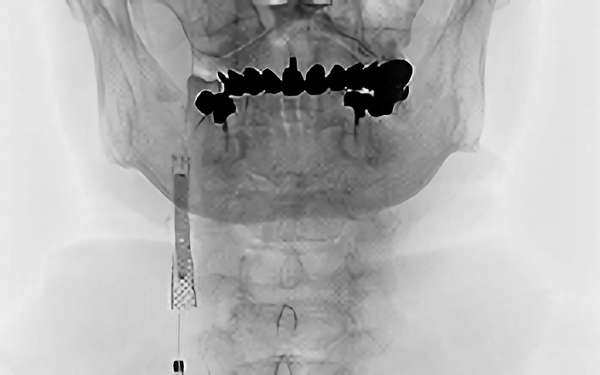

488

'19年5月13日

両側頚部 内頚動脈狭窄症

60代

院内外来